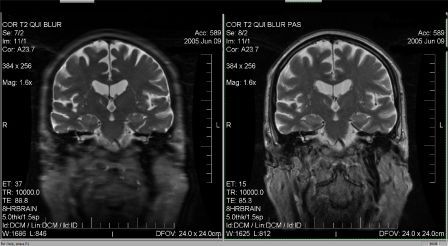

Tu as raison de préciser Higgins que ce n'est pas l'artéfact de troncature... Cet artéfact est dû à une trop grande différence de pondération entre le TE effectif (TE eff) qui va coder pour les lignes centrales de l'espace de Fourier et la pondération du dernier écho du train d'échos (TE max) qui lui, va coder les lignes périphériques de l'espace K. Dans l'exemple ci-dessous, vous pouvez trouver une image volontairement mal paramétrée pour créer du blurring (Train d'écho trop grand) et une image optimisée (paramètres réglés pour que le TE effectif soit au centre du train d'échos). Cet artéfact est souvent confondu avec l'artéfact de mouvement ou est souvent pris pour une mauvaise résolution spatiale...

Pièces jointes : |

blurring anonyme.jpg [ 25.21 Kio | Consulté 49933 fois ]